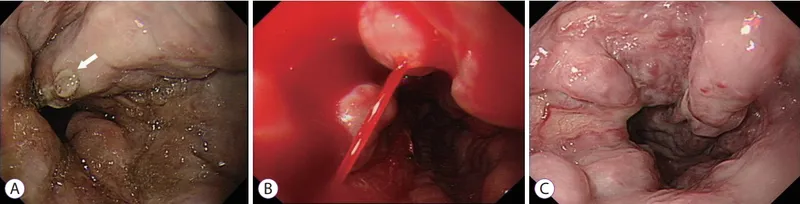

- Urgent Endoscopy (EGD): Within 12 hours.

- Diagnosis & therapy (endoscopic variceal ligation/banding).

- Balloon Tamponade (Sengstaken-Blakemore tube) as a bridge.